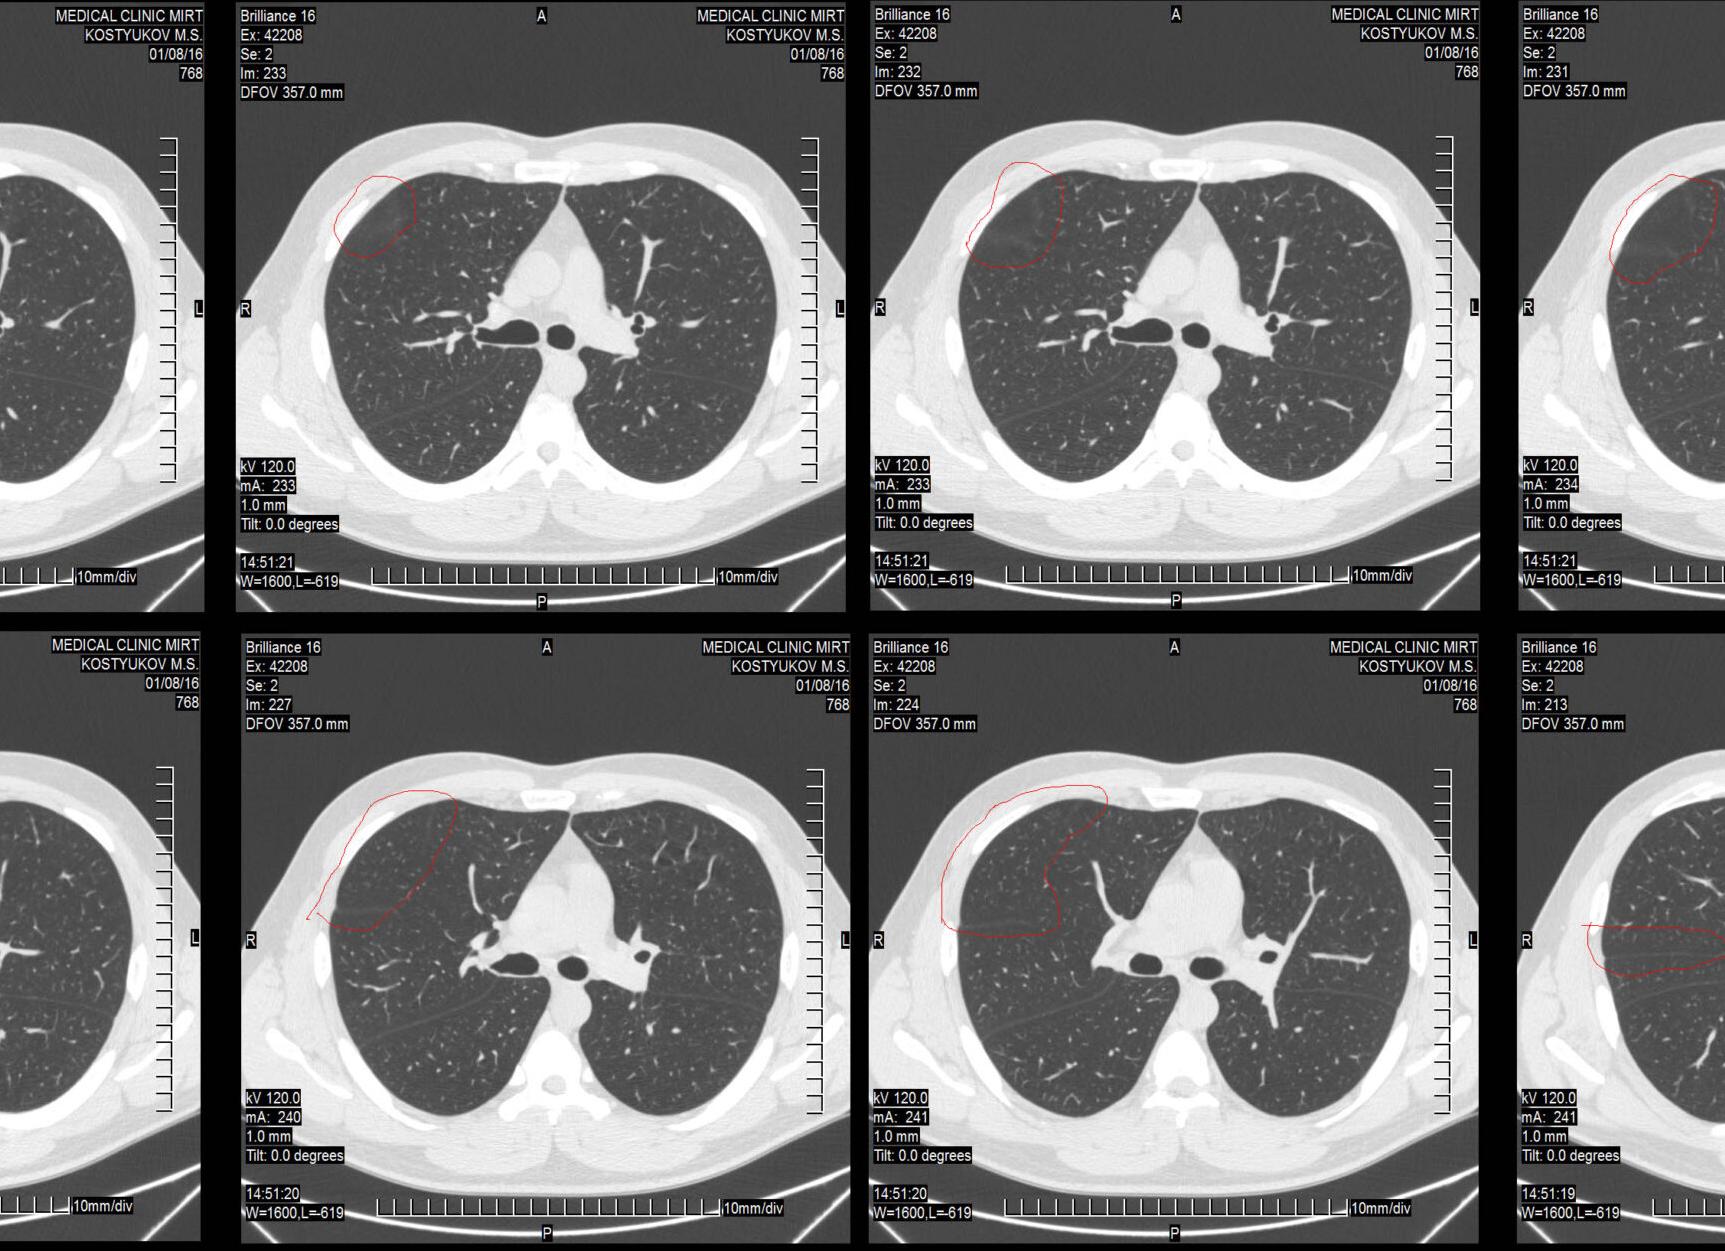

Компьютерная томография (КТ) Органов грудной клетки — детальное послойное рентгеновское изображение органов, а также структур грудной клетки. Исследование дает возможность успешно диагностировать Заболевания легких, Сердца, пищевода, кровеносных сосудов, а также поражения Мягких тканей и органов Средостения.

КОМПЬЮТЕРНАЯ ТОМОГРАФИЯ ЛЕГКИХ — послойное рентгенологическое Исследование легких, основанное на компьютерной реконструкции изображений, получаемых при спиральном сканировании органа узким пучком рентгеновского излучения.

На компьютерной томограмме отчетливо видны легочные сосуды, бронхи, трахея, доли и сегменты легких, внутригрудные лимфатические узлы. Кроме того, при КТ легких можно видеть состояние сердца и сосудов (аорты, легочной артерии, верхней полой вены).